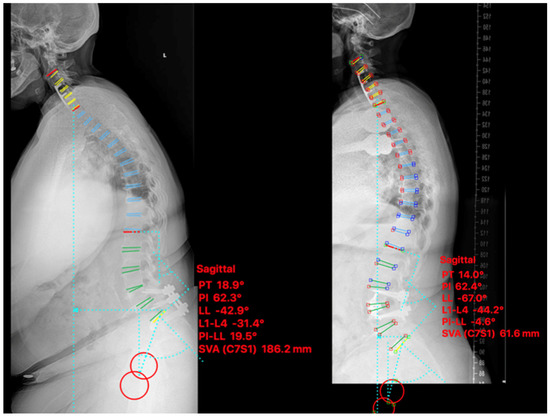

2.4.1. Case I

2.4.2. Case II

2.4.3. Case III